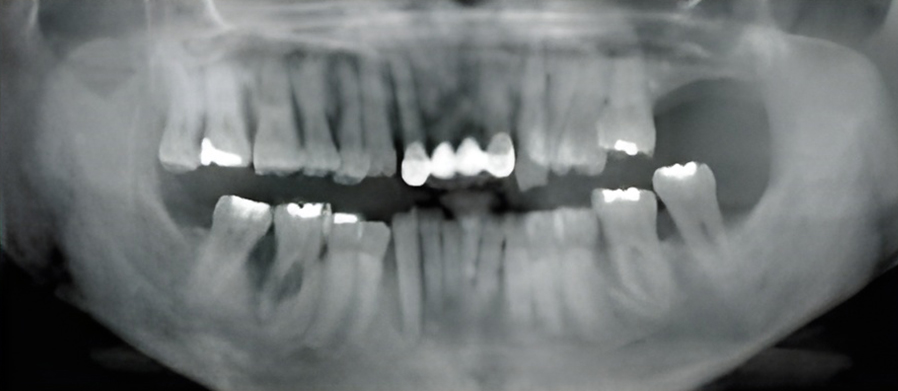

칫솔질과 치실질을 통해 매일 플라그를 제거하지 않으면 박테리아로 인해 잇몸 조직이 붉어지고 부어오르게 됩니다. 염증이 더 심해지면, 치아 주위 조직에 염증이 생기는 치주염으로 진행될 수 있습니다.

치은염을 치료하지 않고 방치하면 플라그가 뿌리로 퍼져 뼈와 연조직에 감염과 손상을 일으킬 수 있습니다. 잇몸이 치아에서 분리되어 물러나기 시작할 수 있으며 잇몸 라인 아래에 주머니가 생겨 플라크와 음식물이 쌓일 수 있습니다.

치주염은 스케일링을 통해 플라그와 치석을 제거하여 치료합니다. 문제가 되는 치주낭 부분을 제거하여 건강한 조직이 치아에 붙을 수 있도록 합니다.

잇몸이 심하게 붓고 피가 자주 나며 치가가 흔들리기도 합니다. 치아 뿌리가 드러나기도 하며 때로는 잇몸에 고름이 나와 음식물을 잘 씹을 수가 없습니다.

잇몸에 고름이 차 있다면 배농이 필요하고, 잇몸을 절개해서 염증조직을 제거하거나 치은이나 뼈를 이식하는 수술을 시행하기도 합니다.

치아 내부 신경이 감염되면 뿌리 끝에 고름이 차는 농양이 생길 수 있습니다. 이로 인해 심한 통증, 부기, 씹기 불편 등이 나타나며 신속한 치료가 필요합니다.